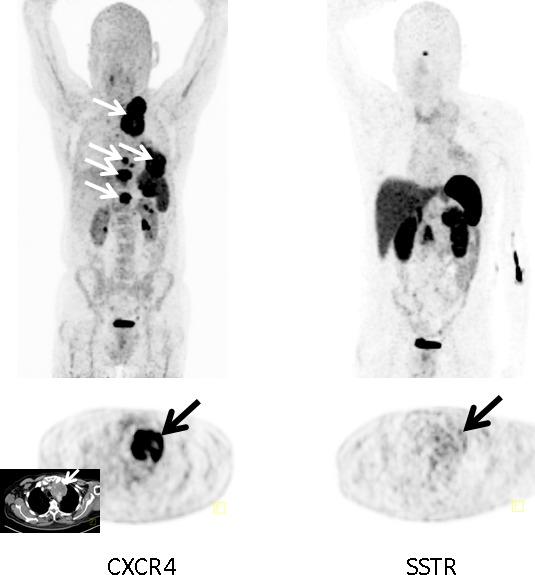

Chemokine receptor CXCR4 is a key factor for tumor growth and metastasis in several types of human cancer. This study investigated the feasibility of CXCR4-directed imaging of small cell lung cancer (SCLC) with positron emission tomography/computed tomography (PET/CT) using the radiolabelled chemokine ligand [68Ga]Pentixafor. 10 patients with primarily diagnosed (n=3) or pre-treated (n=7) SCLC (n=9) or large cell neuroendocrine carcinoma of the lung (LCNEC, n=1) underwent [68Ga]Pentixafor-PET/CT. 2-[18F]fluoro-2-deoxy-D-glucose ([18F]FDG, n=6) and/or somatostatin receptor (SSTR)-directed PET/CT with [68Ga]DOTATOC (n=5) and immunohistochemistry (n=10) served as standards of reference. CXCR4-PET was positive in 8/10 patients and revealed more lesions with significantly higher tumor-to-background ratios than SSTR-PET. Two patients who were positive on [18F]FDG-PET were missed by CXCR4-PET, in the remainder [68Ga]Pentixafor detected an equal (n=2) or higher (n=2) number of lesions. CXCR4 expression of tumor lesions could be confirmed by immunohistochemistry. Non-invasive imaging of CXCR4 expression in SCLC is feasible. [68Ga]Pentixafor as a novel PET tracer might serve as readout for confirmation of CXCR4 expression as prerequisite for potential CXCR4-directed treatment including receptor-radio(drug)peptide therapy.

趋化因子受体CXCR4是多种人类癌症中肿瘤生长和转移的关键因素。本研究使用放射性标记的趋化因子配体[68Ga]喷替沙福,通过正电子发射断层扫描/计算机断层扫描(PET/CT)研究了针对CXCR4的小细胞肺癌(SCLC)成像的可行性。10例初诊(n = 3)或经预处理(n = 7)的SCLC(n = 9)或肺大细胞神经内分泌癌(LCNEC,n = 1)患者接受了[68Ga]喷替沙福-PET/CT检查。2-[18F]氟-2-脱氧-D-葡萄糖([18F]FDG,n = 6)和/或使用[68Ga]奥曲肽的生长抑素受体(SSTR)导向的PET/CT(n = 5)以及免疫组织化学(n = 10)作为参考标准。CXCR4-PET在8/10例患者中呈阳性,与SSTR-PET相比,显示出更多具有显著更高肿瘤与背景比值的病灶。2例[18F]FDG-PET呈阳性的患者被CXCR4-PET漏诊,在其余患者中,[68Ga]喷替沙福检测到的病灶数量相等(n = 2)或更多(n = 2)。肿瘤病灶的CXCR4表达可通过免疫组织化学得到证实。SCLC中CXCR4表达的无创成像是可行的。[68Ga]喷替沙福作为一种新型PET示踪剂,可能作为确认CXCR4表达的检测手段,这是包括受体放射性(药物)肽治疗在内的潜在CXCR4导向治疗的前提条件。